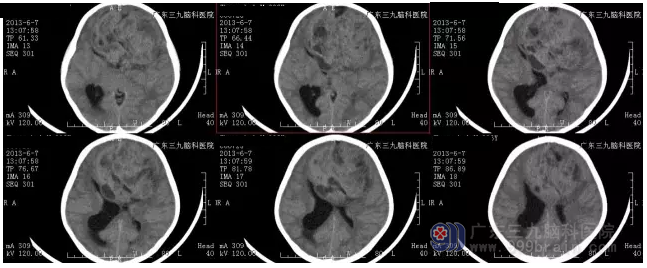

入院后完善检查,术前CT显示可见多发斑片状低密度影,病变范围9.7CM×7.33CM,鉴于患儿病情危重,科室在急诊全麻下行双侧额叶巨大占位性病变切除术,手术由神经外一科主任张良主刀完成,术程顺利,术后诊断:双侧额叶巨大肿瘤。术后病理:间变型脑室外神经细胞瘤 WHOⅢ级。

图2:术前CT显示病变范围9.7CM×7.33CM